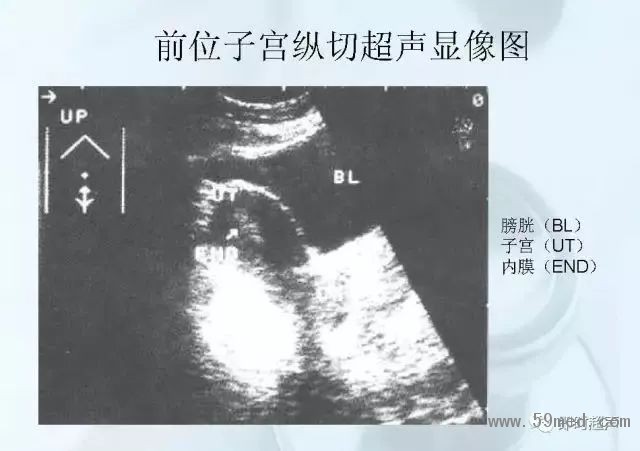

新聞中心 收藏!正常B超解剖圖譜,超實用!